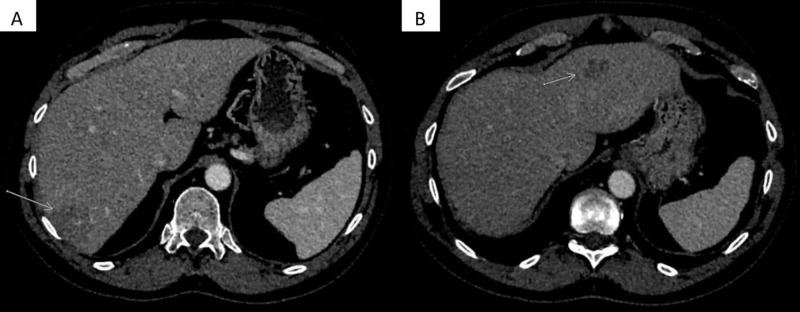

A 59-year-old male presented with a two-month history of abdominal pain and was found to have an obstructing cecal mass. Colonoscopy and biopsy confirmed invasive adenocarcinoma. Immunohistochemical analyses for mismatch repair (MMR) proteins revealed the loss of MLH1 as well as PMS2 in cancerous nuclei, which makes the tumor MMR deficient. Negative germline testing for MMR proteins ruled out the Lynch syndrome. After negative staging computerized tomography scan for distant metastases, he underwent ileocolectomy with ileotransverse colonic anastomosis. Final pathological analysis revealed poorly differentiated adenocarcinoma with signet ring features, negative margins, and 3/22 lymph nodes positive, classified as stage IIIB (T4aN1bM0). Adjuvant chemotherapy with modified FOLFOX (leucovorin calcium/folinic acid, fluorouracil, and oxaliplatin) was started without the use of any growth factor support. After cycle 9 of 12, he developed mild transaminitis, carcinoembryonic antigen elevation, and interval development of two heterogeneously enhancing hepatic lesions. Biopsy of both of these lesions revealed extramedullary hematopoiesis (EMH), with no evidence of metastatic disease. He completed adjuvant chemotherapy without complication, and these liver lesions have decreased in size during the follow-up period of almost two years thus far. EMH is extremely rare in patients with colon cancer. Contributing factors include therapy-specific (growth factor support), bone marrow suppression secondary to chemotherapy and radiation therapy, and tumor-specific factors (cytokine and growth factors released by the tumor). To the best of our knowledge, this is the first case report of EMH in an MMR deficient colon cancer patient on adjuvant FOLFOX. MMR-deficient tumors show signs of a high degree of infiltration with CD8+ cytotoxic T lymphocytes as well as helper T cells, leading to increased production of cytokines, such as interferon-γ. This could be a potential etiology behind EMH in our patient who was MMR deficient. The role of the MMR-deficient state in the development of EMH should be explored further.

一名59岁男性因腹痛两个月就诊,检查发现盲肠有梗阻性肿物。结肠镜检查及活检确诊为浸润性腺癌。错配修复(MMR)蛋白的免疫组化分析显示癌细胞核中MLH1及PMS2缺失,提示肿瘤MMR缺陷。MMR蛋白种系检测阴性排除了林奇综合征。在分期计算机断层扫描未发现远处转移后,他接受了回盲部切除术及回肠横结肠吻合术。最终病理分析显示为低分化腺癌,伴有印戒细胞特征,切缘阴性,22枚淋巴结中有3枚阳性,分类为IIIB期(T4aN1bM0)。开始采用改良FOLFOX方案(亚叶酸钙/甲酰四氢叶酸、氟尿嘧啶和奥沙利铂)进行辅助化疗,未使用任何生长因子支持。在12周期的第9周期后,他出现轻度转氨酶升高、癌胚抗原升高,并出现两个不均匀强化的肝脏病变。这两个病变的活检显示为髓外造血(EMH),无转移瘤证据。他顺利完成了辅助化疗,在迄今近两年的随访期间,这些肝脏病变大小减小。EMH在结肠癌患者中极为罕见。相关因素包括治疗特异性(生长因子支持)、化疗和放疗继发的骨髓抑制以及肿瘤特异性因素(肿瘤释放的细胞因子和生长因子)。据我们所知,这是首例关于接受辅助FOLFOX治疗的MMR缺陷型结肠癌患者发生EMH的病例报告。MMR缺陷型肿瘤表现出CD8+细胞毒性T淋巴细胞及辅助性T细胞高度浸润的迹象,导致细胞因子如干扰素-γ的产生增加。这可能是我们这位MMR缺陷患者发生EMH的潜在病因。MMR缺陷状态在EMH发生中的作用应进一步探讨。